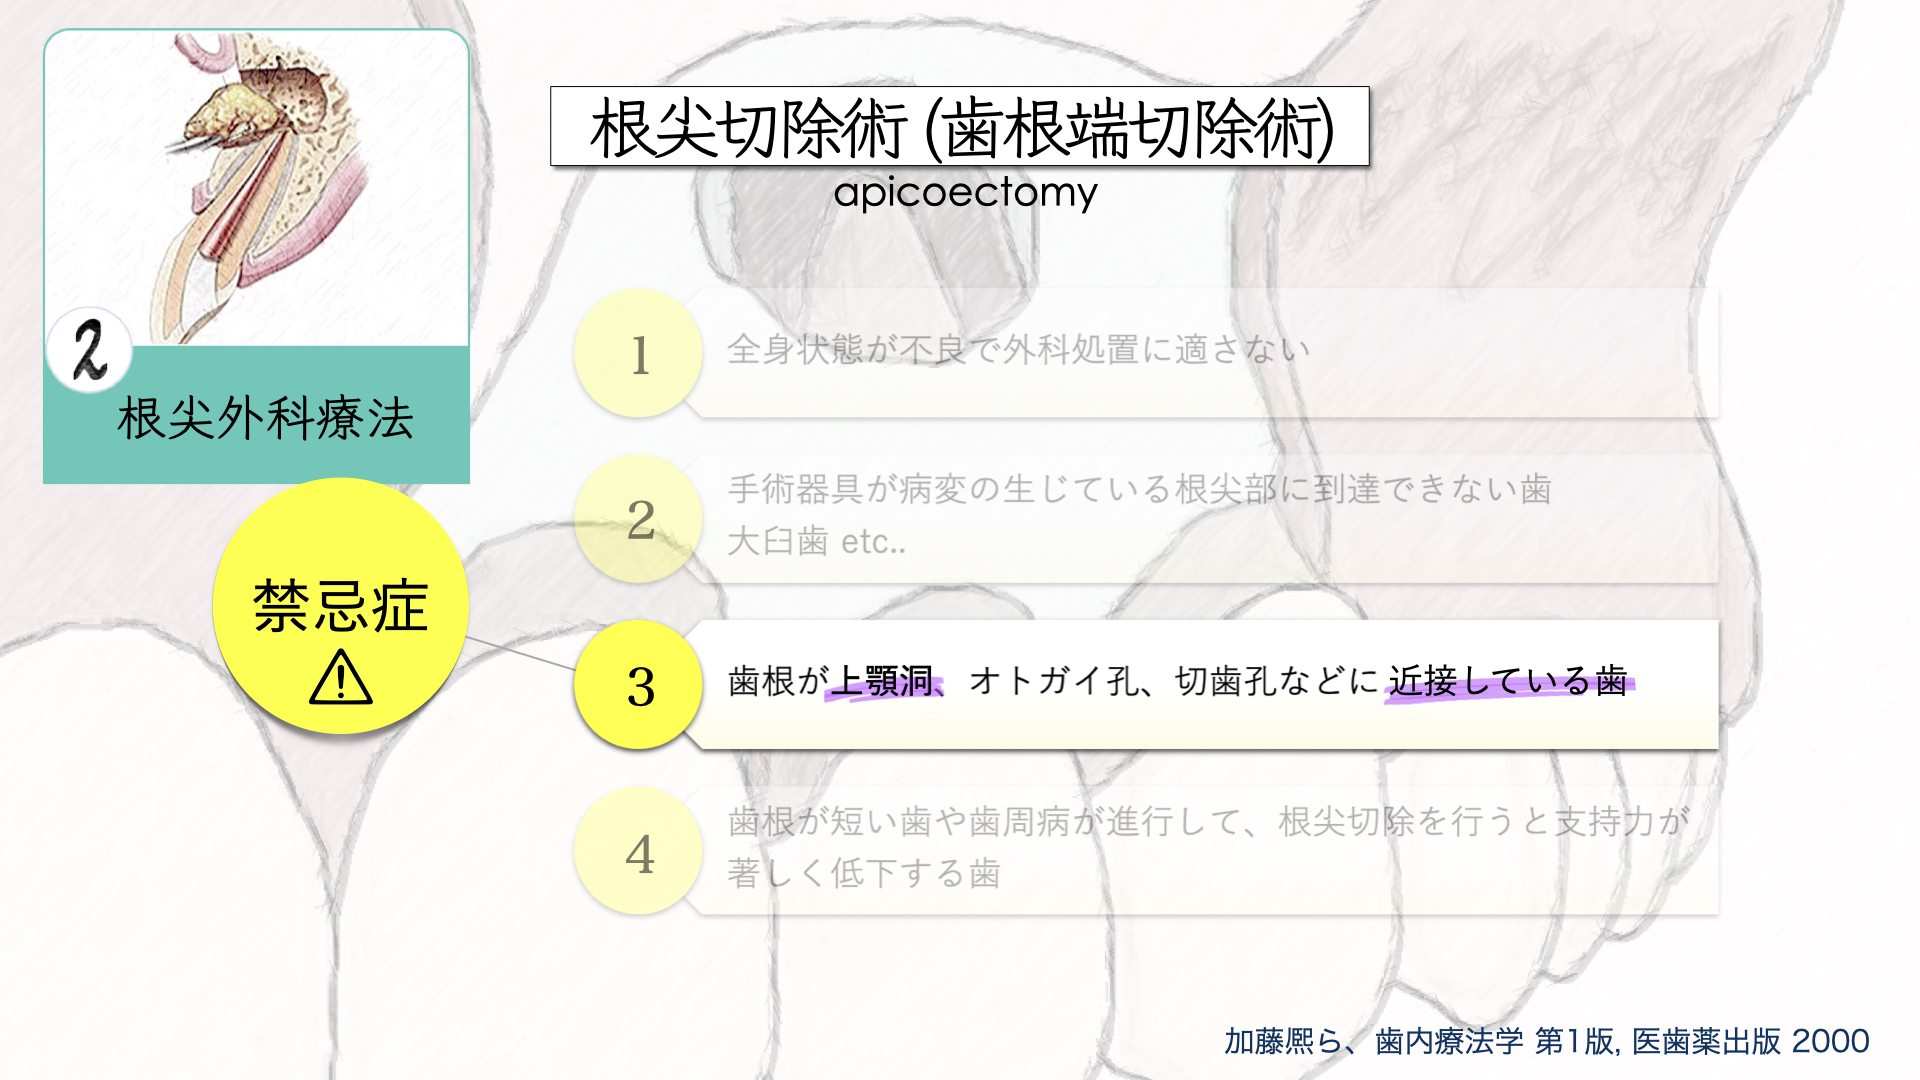

教科書によると、この部位は適応症でなく、一般的には意図的再植の適応症にはなりますが、このような歯根が離開している歯を一度抜歯するのは破折のリスクがあります。

適応症ではないのは大口蓋動脈の存在です。